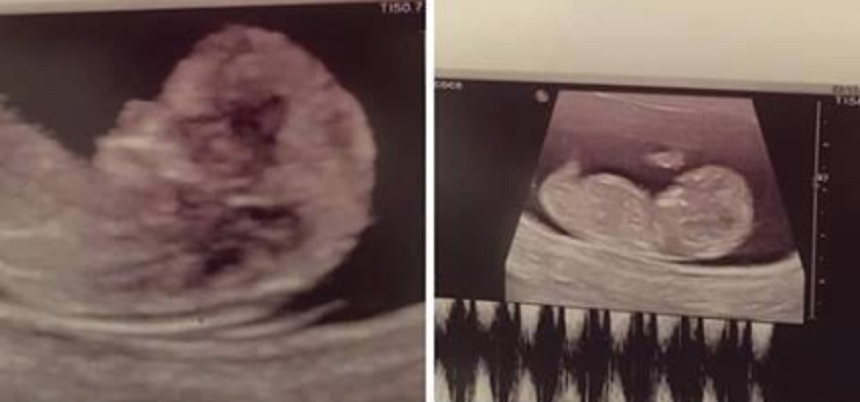

Aceasta e prima ecografie pe care a făcut-o sora Mariei Constantin. Sursa foto: Facebook

Maria Constantin, în culmea fericirii! Au apărut imagini cu prima ecografie